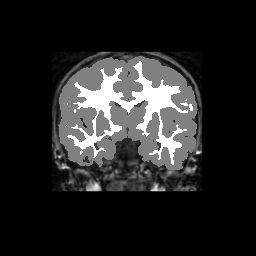

Accuracy is reported as Dice overlaps between a tool's segmentation and the Internet Brain Segmentation Repository (IBSR) manual segmentation for each of the 18 IBSR subjects. The inter-tool comparison (on the left below) shows the median Dice coefficient for each tissue class. The overlaps for FSL (from which the median values are drawn) are shown in the plot on the right.

Overlap coefficients for each tissue class are shown here for each IBSR subject. Select a subject below to see the FSL results compared to other tools.